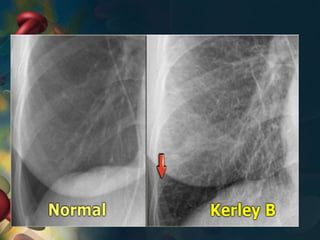

• Enlarged left ventricle on X-ray

• Enlarged left atrium on X-ray